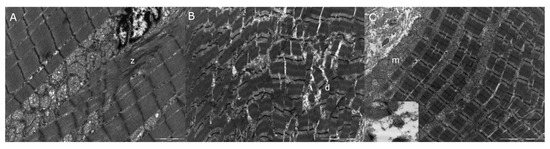

3.4. Transmission Electron Microscopy